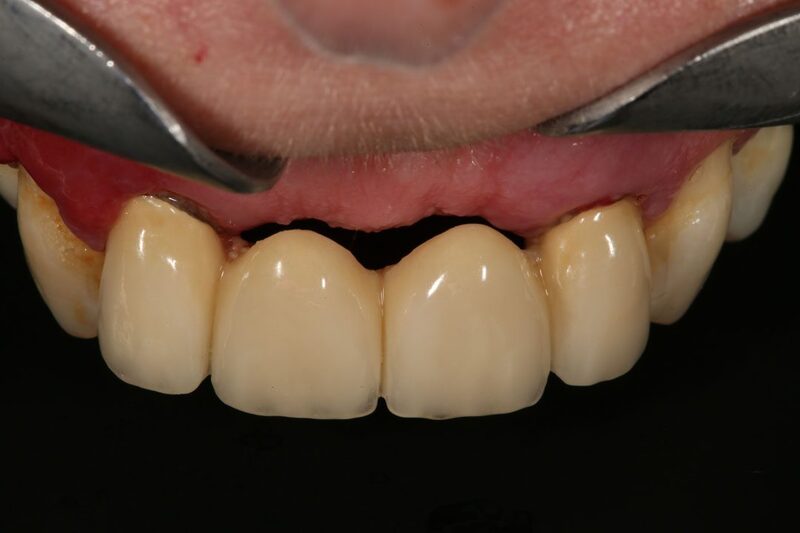

2.3. Đảm bảo thẩm mỹ trắng và thẩm mỹ hồng cho răng Implant

Răng cửa nằm ở vị trí dễ thấy nhất khi cười hay giao tiếp. Do đó, khi cấy răng Implant tại vị trí răng cửa, không chỉ cần đảm bảo chức năng ăn nhai mà còn phải chú trọng đến thẩm mỹ trắng và thẩm mỹ hồng:

• Về thẩm mỹ trắng: Là thẩm mỹ của mão răng, để đáp ứng được thẩm mỹ trắng, mão răng cần có màu sắc tự nhiên và độ trong mờ chuyển màu tự nhiên như răng thật.

• Về thẩm mỹ hồng: Nướu có màu sắc hồng tự nhiên, gai nướu nhọn, không bị ánh đen.

Một chiếc Implant răng cửa cần đáp ứng được chức năng thẩm mỹ trắng và thẩm mỹ hồng để mang lại cho hài sự hài hòa cho khuôn mặt

Các phương pháp trồng răng Implant truyền thống đều không đảm bảo thẩm mỹ ở cả 2 yếu tố trên. Do đó, cô chú/anh chị nên tìm hiểu các phương pháp trồng răng hiện đại, một trong số đó bao gồm giải pháp trồng răng Implant cá nhân hóa DCT có thể giải quyết được vấn đề thẩm mỹ của răng, lợi như trên.

• Thẩm mỹ như răng thật: Chức năng thẩm mỹ hồng được đảm bảo nhờ vào việc sử dụng trụ lành thương để tái lập mô nha chu, trụ phục hình cá nhân hóa được sản xuất theo hình thể giải phẫu răng - lợi của từng cá nhân. Bên cạnh đó, mão răng sứ  3D Pro Multilayer có độ trong mờ ổn định, đảm bảo chức năng thẩm mỹ trắng như răng thật.